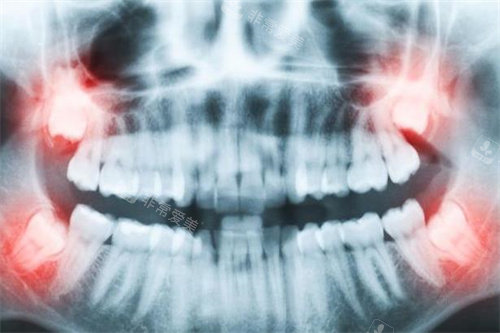

牙齿拍片图